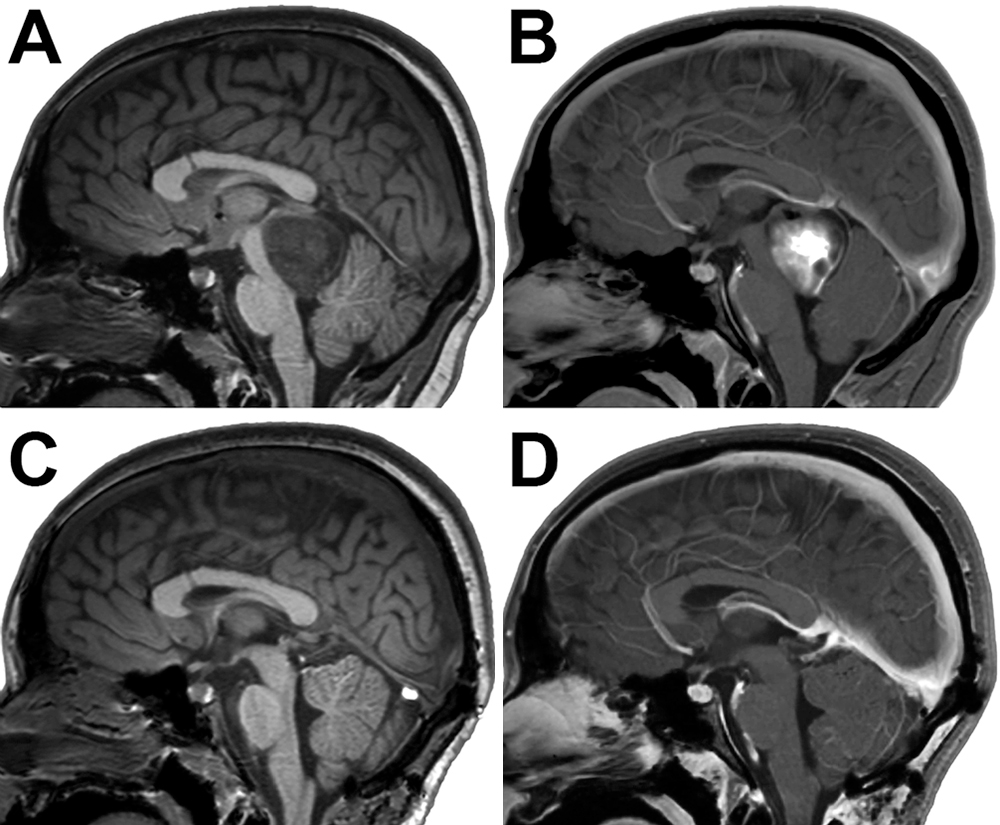

術(shù)后影像學(xué)證實(shí)了全切除(圖2C和D)和腫塊對(duì)導(dǎo)水管的影響的緩解?;颊叩哪X室繼續(xù)變小??紤]到她腫瘤的低級(jí)別組織病理學(xué),她不需要輔助治療。術(shù)后6個(gè)月(初次呈現(xiàn)后11.5年),患者恢復(fù)良好。

圖2:發(fā)現(xiàn)頂蓋膠質(zhì)瘤并隨后切除。A和B:患者11歲時(shí)獲得矢狀t1加權(quán)MR圖像,無(A)加(B)釓,顯示一個(gè)不均勻強(qiáng)化的顱蓋病灶,對(duì)大腦導(dǎo)水管產(chǎn)生腫塊效應(yīng)。她隨后接受開顱手術(shù)切除腫瘤。C和D:術(shù)后矢狀t1加權(quán)MR圖像,顯示腫瘤全部切除。值得注意的是,由于VP分流器的持續(xù)作用,患者的腦室大小始終保持穩(wěn)定。